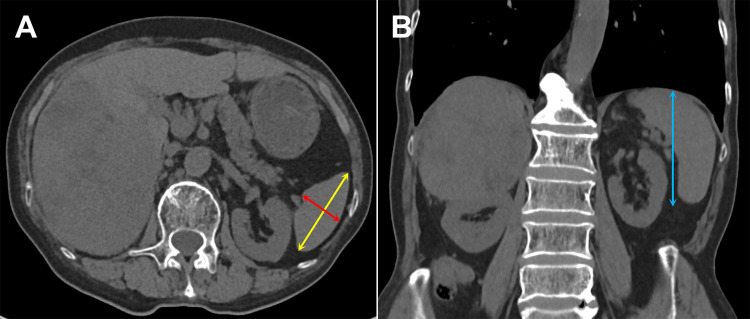

Purpose: The spleen serves as an important immune organ which influences the anti-tumor immune response by modulating the immune microenvironment. This study investigated the prognostic impact of spleen volume (SV) on the survival in hepatocellular carcinoma (HCC) patients receiving immune checkpoint inhibitors (ICIs).

Patients and methods: This retrospective study included 224 HCC patients treated with ICIs, categorized into Higher and Lower SV groups by median SV and further into SV increased and Non-SV increased groups based on changes in SV at 3 months after ICIs. Kaplan-Meier curves and Cox regression models were used to evaluate the influence of SV and clinical indicators on progression-free survival (PFS) and overall survival (OS). Independent prognostic factors identified via multivariate analysis were incorporated into nomograms, with their accuracy assessed using concordance index (C-index), time-dependent receiver operating characteristic (ROC) and calibration curves. Restricted cubic spline (RCS) analysis was conducted to assess the relationship between baseline SV and survival.

Results: The Higher SV and SV increased groups demonstrated shorter PFS and OS compared to the Lower SV and Non-SV increased groups, respectively. These results were consistent with different regimens in the Child A. The C-index of nomogram for PFS were 0.700 (0.678-0.721) and OS 0.733(0.709-0.757). The ROC and calibration curves confirmed robust discrimination and predictive accuracy of models. RCS analysis revealed a nonlinear association between baseline SV and survival risk, providing a more comprehensive overview of SV in relation to survival in HCC patients treated with ICIs.

Conclusion: The baseline SV and its relative change at three months after treatment are expected to become routine imaging makers for predicting survival in HCC patients receiving ICIs, which consequently contributes to their clinical management.